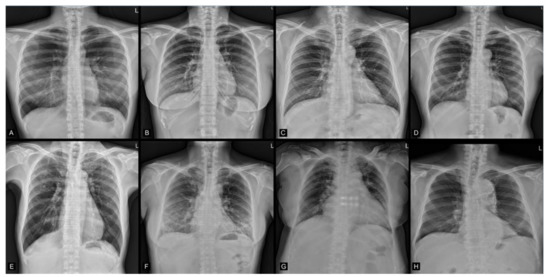

3.3. Group Summarized Activation Maps